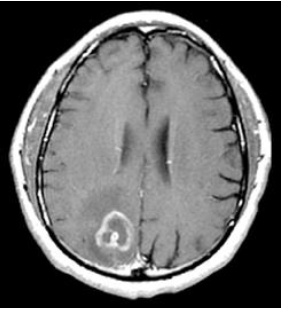

Paciente masculino, 32 anos, AIDS (CD4=98), chega ao PS com queixa de cefaleia há 2 semanas, com diminuição da força em MSE e febre. Realizada tomografia computadorizada de crânio, evidencia a imagem abaixo.

Qual hipótese diagnóstica é a mais provável?